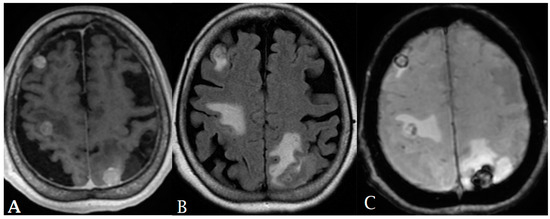

- Kickingereder, P.; Wiestler, B.; Sahm, F.; Heiland, S.; Roethke, M.; Schlemmer, H.-P.; Wick, W.; Bendszus, M.; Radbruch, A.; Jalaguier-Coudray, A.; et al. Primary Central Nervous System Lymphoma and Atypical Glioblastoma: Multiparametric Differentiation by Using Diffusion-, Perfusion-, and Susceptibility-weighted MR Imaging. Radiology 2014, 272, 843–850. [Google Scholar] [CrossRef]

- Blasel, S.; Jurcoane, A.; Franz, K.; Morawe, G.; Pellikan, S.; Hattingen, E. Elevated peritumoural rCBV values as a mean to differentiate metastases from high-grade gliomas. Acta Neurochir. 2010, 152, 1893–1899. [Google Scholar] [CrossRef]